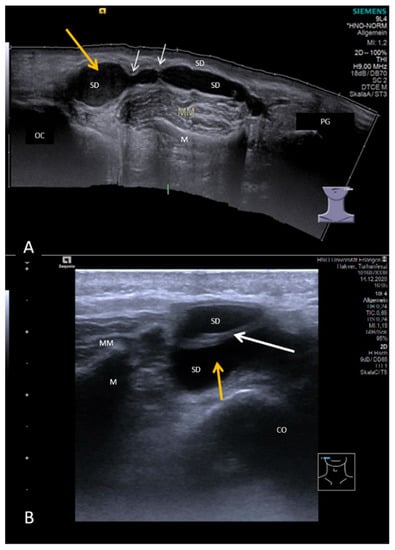

3.2. Findings in Normal Anatomy in Major Salivary Glands

3.3. Ultrasonographic Signs of Acute and Chronic Inflammatory and Obstructive Sialadenitis

3.3.1. Acute or Subacute Primary Non-Obstructive Microbial Sialadenitis

3.3.2. Obstructive Sialadenitis Caused by Sialolithiasis

3.3.3. Non-Sialolithiasis-Caused Unspecific Sialadenitis with Sialodochitis and/or Duct Stenosis with Primary or Secondary Obstruction